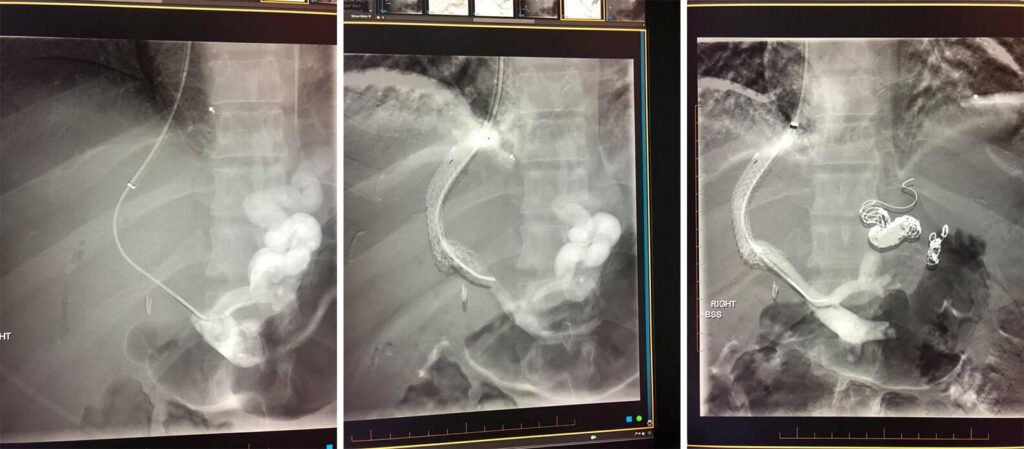

Case of the week: Diaylsis patient with decrease in functioning of AV fistula - competing accessory vein needs to be shut down to fully route flow to AV fistula

Plug embolization of a competing vein for a successful maturation of the left arm AV fistula.

(*closing off of larger vein that takes blood away from a normal AV fistula)

Photo 1 - Accessory vein to shut down

Photo 2- Plug insertion into competing accessory vein

Photo 3- Full functioning AV fistula due to plug embolization